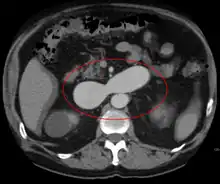

An arterial venous malformation of the left kidney and a simple cyst of the right kidney

An arterial venous malformation of the left kidney leading to aneurysmal dilatation of the left renal vein and inferior vena cava